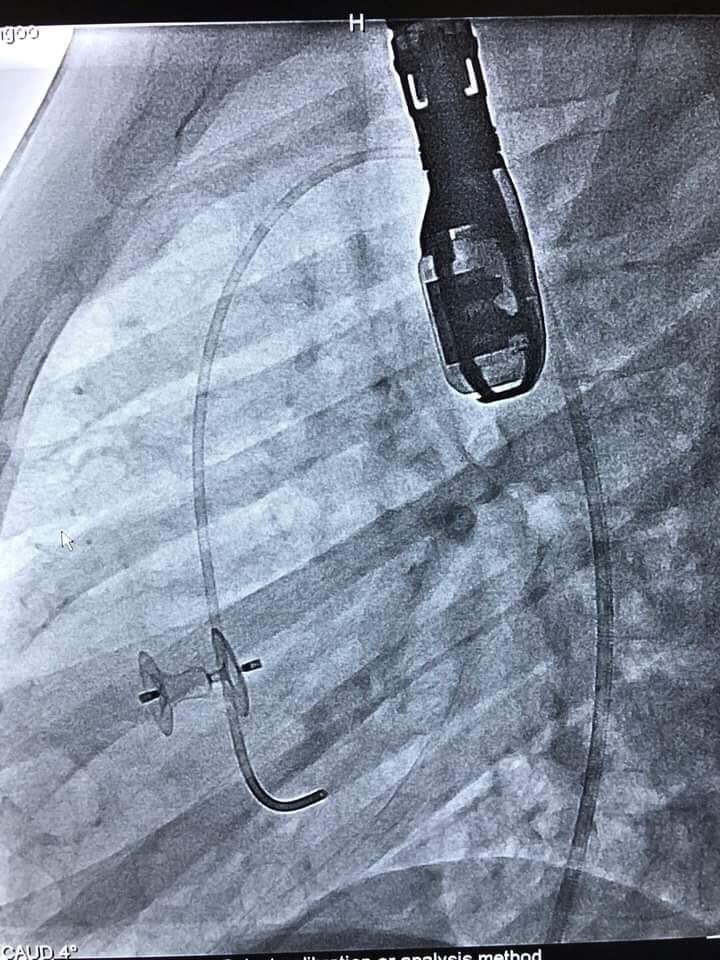

Эх хүүхдийн эрүүл мэндийн үндэсний төвийн Хүүхдийн эмнэлгийн Зүрхний катетер ангиографийн баг Монгол Улсад анх удаа судсан дотуурх мэс заслыг амжилттай хийж гүйцэтгэснийг ЭМЯ мэдээлжээ. Тодруулбал, таван эмч, хоёр сувилагч, нэг техникчээс бүрдсэн тус баг энэ сарын 6-7–нд Бүгд Найрамдах Индонез улсын эмч мэргэжилтнүүдтэй хамтран зүрхний төрөлхийн гажиг болох Ховдол хоорондын таславчийн цоорхойг “окклюдер”-аар хаах судсан дотуурх мэс заслыг дөрвөн хүүхдэд амжилттай хийсэн байна.

Ийнхүү дэлхийн өндөр хөгжилтэй орнууд нэвтрүүлж эхлээд хоёр жил болж буй энэхүү шинэ технологийг ЭХЭМҮТ-ийн хамт олон нэвтрүүлж, анхны мэс заслаа амжилттай гүйцэтгэжээ.